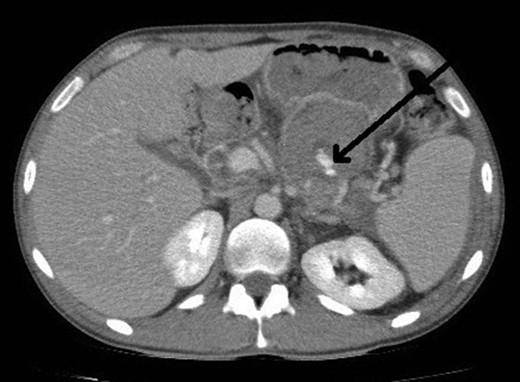

He presented to the local tertiary referral centre complaining of chest pain and the normal ECG, cardiac markers and chest X-ray suggested a non-cardiac cause for the pain. He remained haemodinamically stable and was further investigated with an abdominal ultrasound (USS) and a contrast enhanced computed tomography (CT). The latter demonstrated a 5 × 3.8 cm2 pseudoaneurysm posterior to the stomach and superior to the body of the pancreas but of unclear origin. It also showed a large subcapsular splenic haematoma measuring 10.8 × 7.7 cm2 and a perisplenic collection (Fig. 1).

CT abdomen image shows flow in pseudoaneurysm (arrow) posterior to the stomach and the subcapsular splenic haematoma.